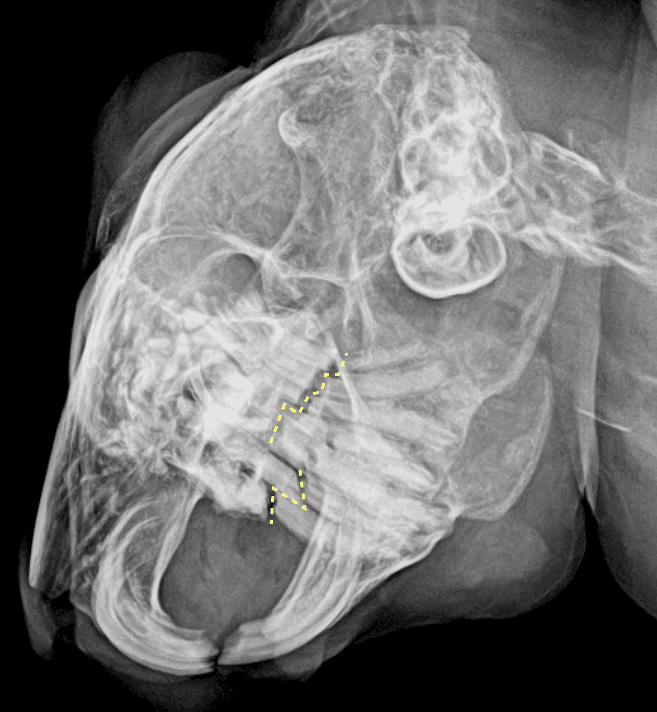

身体検査にて口内の歯の咬み合わせが悪い所見が認められたため、鼻腔や臼歯の評価をするためにレントゲン検査を実施いたしました。

(↑咬み合わせのラインは正常では一直線になります)

検査の結果、臼歯の不正咬合が認められ、慢性鼻炎の原因と考えられました。